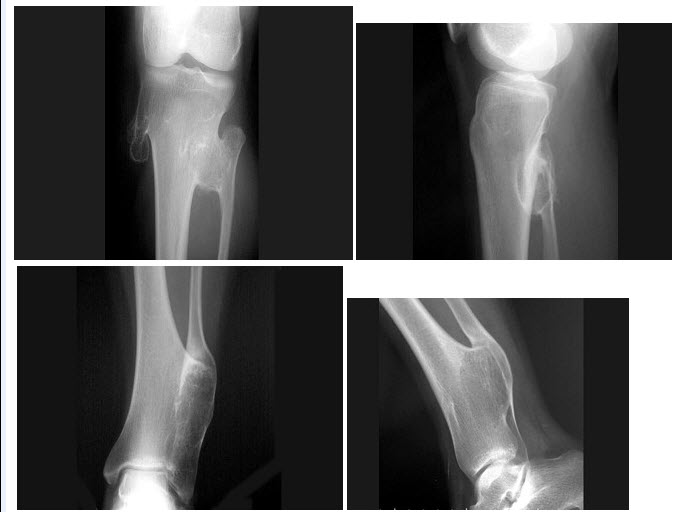

14、单项选择题

左膝关节酸胀不适,摄片发现左胫骨上段局限性骨质改变如图示,最可能的诊断是()

D.结肠肝曲

B.骨质疏松

C.骨间断性生长痕